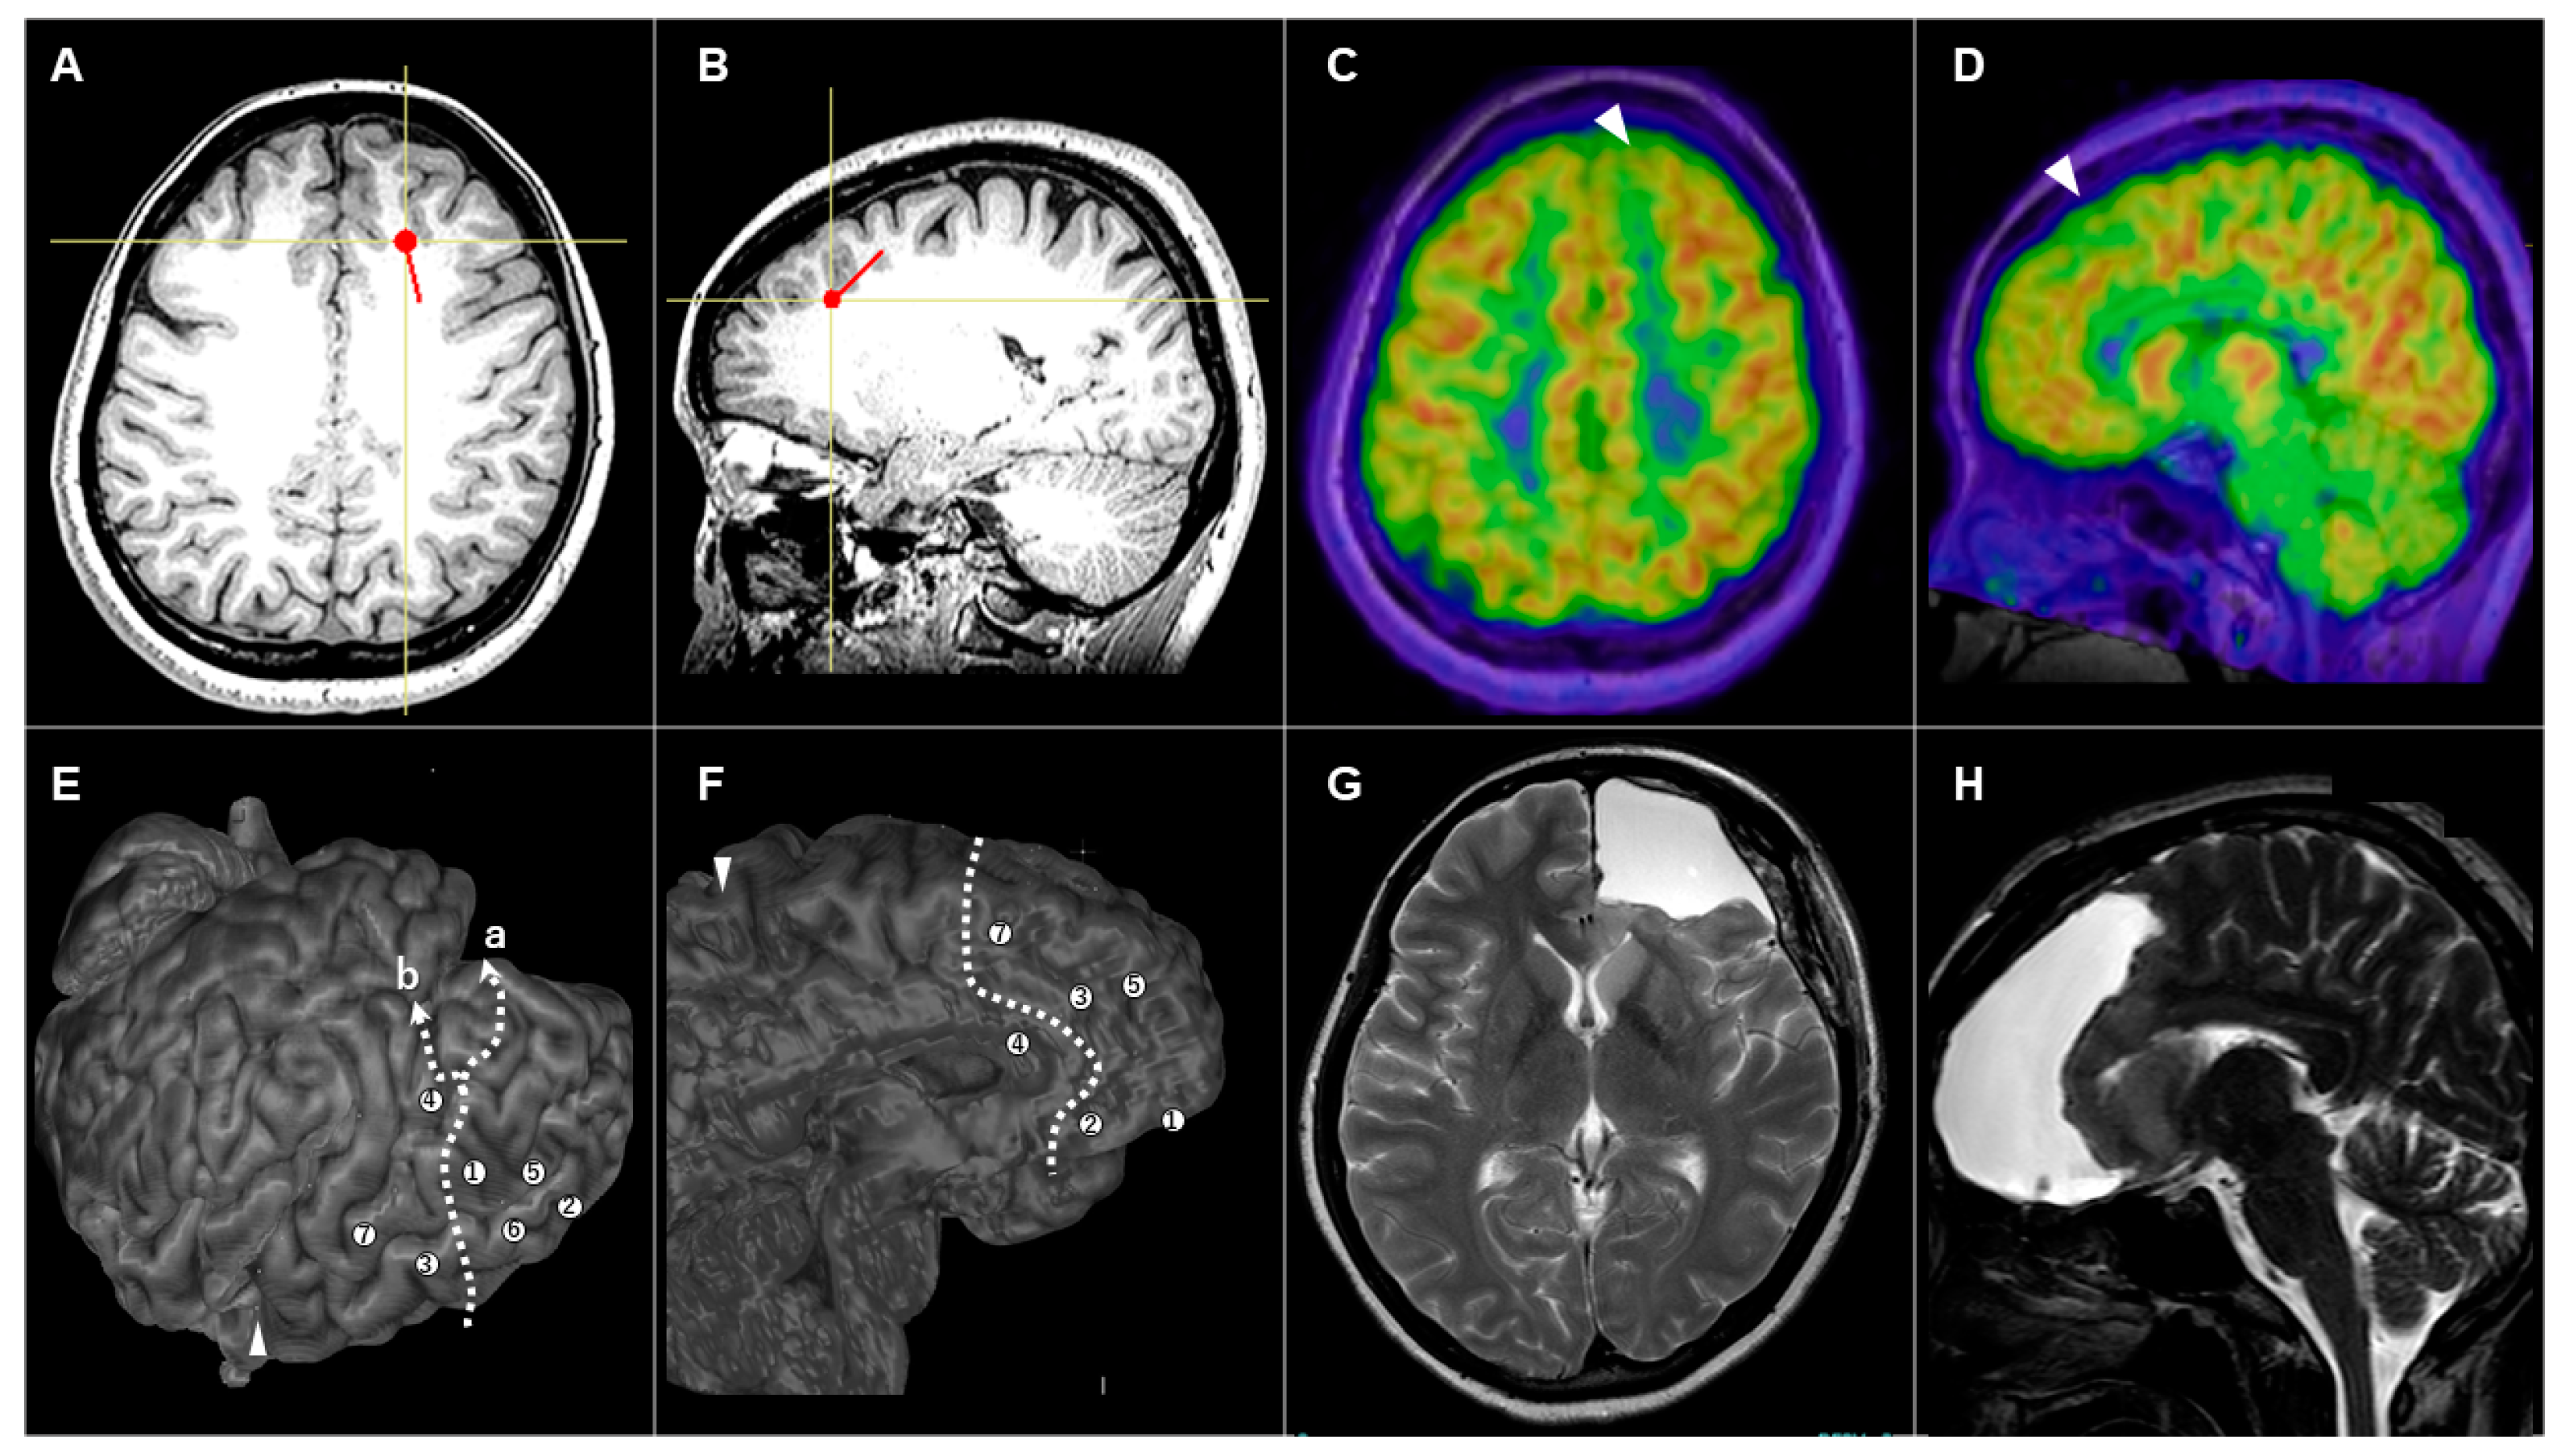

3.3.2. Patient #5 (AWC#2) (Figure 3)